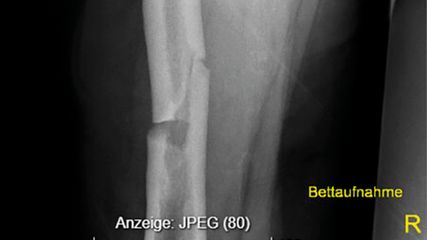

In einer chinesischen Studie war der monoklonale Antikörper Romosozumab bezüglich Zunahme der Knochendichte bei Risikopatient:innen Denosumab überlegen. Eine italienische Untersuchung kam zu dem Schluss, dass alle Osteoporosetherapeutika langfristig einen guten Schutz vor Frakturen bieten, wenn auch in unterschiedlichem Ausmaß.

Eine Studie zum Vergleich zweier monoklonaler Antikörper zur Osteoporosetherapie bezog 70 erwachsene Teilnehmer:innen ein, die seit mindestens einem Jahr ≥5mg Prednisolon eingenommen hatten. Nach der Randomisierung erfolgte eine 12-monatige Therapie mit monatlich 210mg Romosozumab oder 60mg Denosumab alle sechs Monate. Danach schloss sich ein Jahr Denosumab für beide Gruppen an. Die vorbestehende Behandlung mit Kalzium und Vitamin D wurde während der Studie fortgeführt. Alle Teilnehmer:innen hatten ein mittleres oder hohes Risiko für osteoporotische Frakturen.

Nach 12 Monaten zeigte sich ein signifikanter Anstieg der Knochendichte (BMD) in der Lendenwirbelsäule bei 7,3% in der Romosozumab-Gruppe und 2,3% in der Denosumab-Gruppe. Nach Bereinigung der Ergebnisse um die BMD-Basiswerte, Alter, Geschlecht und andere Osteoporosefaktoren wurde immer noch ein signifikanter Unterschied zwischen den Behandlungsgruppen festgestellt (p<0,001). Die Veränderungen der BMD in der Hüfte und im Oberschenkelhals waren ebenfalls signifikant, ohne dass ein Unterschied zwischen den Gruppen ermittelt wurde.

Der Anteil an Patient:innen, die nach zwei Jahren Behandlung den STE erreichten, variierte je nach Behandlung, Frakturtyp und Ausmaß der Risikosenkung. Unter Einschluss aller Frakturarten wurde zu diesem Zeitpunkt eine Risikominderung von 24,2% (Bisphosphonate), 48,5% (Denosumab) und 62,9% (Teriparatid) erreicht. Bezogen auf Wirbelkörperfrakturen waren die entsprechenden Anteile 24,4%, 49,1% und 62,9% und bei Hüftfrakturen 21,4%, 46,9% und 61,4%.